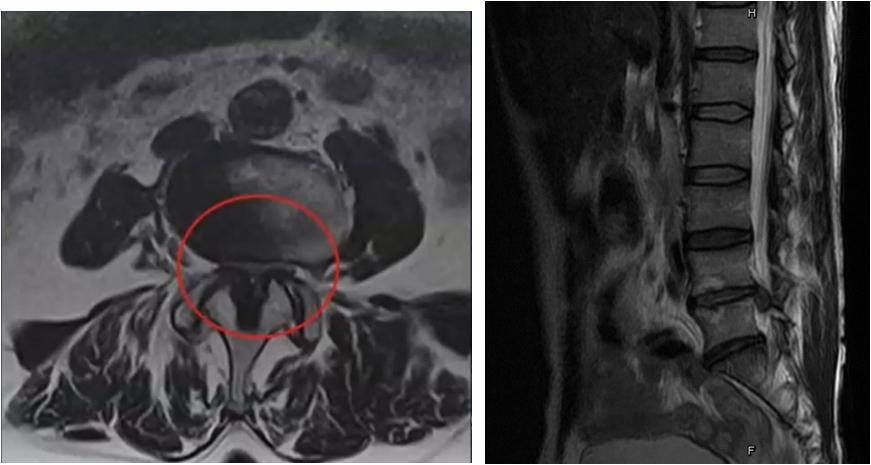

骨头没问题不代表真的没问题,很多时候为了看清楚关节周围的肌肉、韧带等软组织或者判断新鲜还是陈旧性骨折时,就需要进行MRI检查。MRI在骨科疾病的诊断中有两个最重要的应用,就是脊柱和膝关节。MRI在脊柱可以很好地显示椎体、椎间盘、硬膜囊、神经等结构,还能显示椎间盘变性、硬膜囊受压、马尾神经紊乱等病理改变。MRI在膝关节可以显示半月板、交叉韧带、关节内液体等结构。